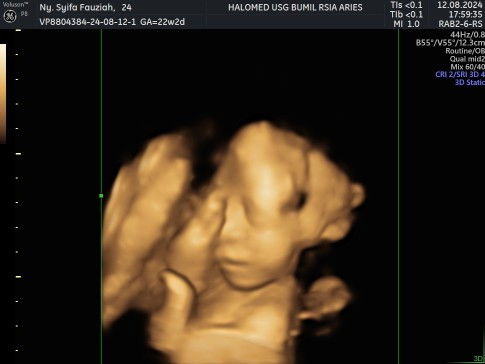

usia kehamilan 30 minggu itu kira²BB bayi brp kilo ya? Anak yg pertama kan lahiran sesar

Apakah nanti anak yg ke 2 bisa lahiran normal?